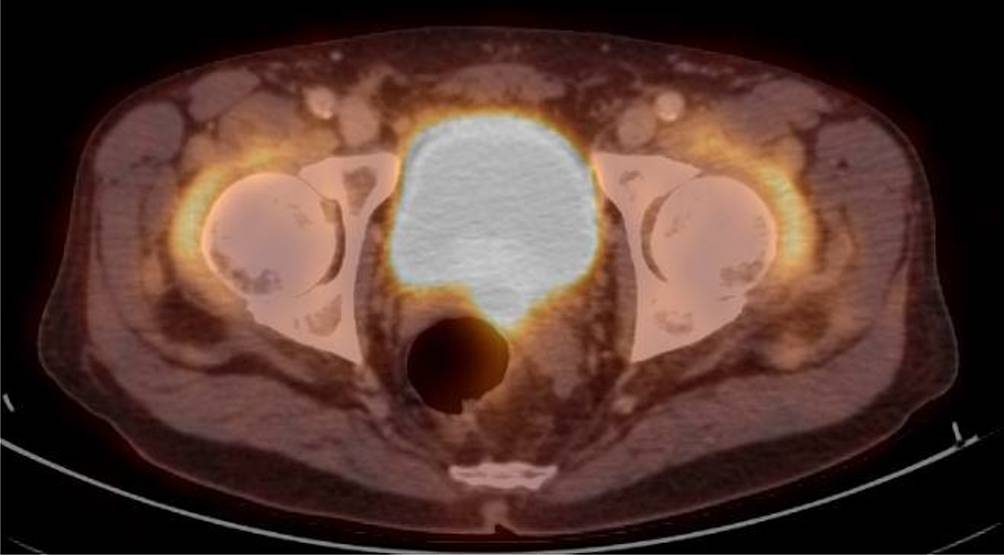

Abb. 1

18F-FDG-Anreicherungen unmittelbar anterolateral der Capites femores bei einem Patienten mit Polymyalgia rheumatica (axial)

Patienten der Fallgruppe mit PMR zeigten auch nach Bonferroni-Korrektur einen signifikant höheren Messwert des SUVmax als nicht an PMR erkrankte Patienten der Kontrollgruppe (p < 0,001) (Tab. 1) – hierunter auch Patienten mit RA und SPA – an allen untersuchten Regionen. Die Anreicherungen projizierten sich auf die großen Gelenke des Körperstammes, die Sitzbeine (Abb. 1 und 2), sowie die interspinal lumbale Region.